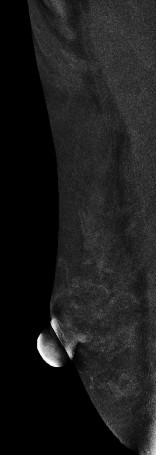

低能图像

常规检查:右乳偏外下象限见模糊类圆形结节影,CESM显示结节不均匀强化